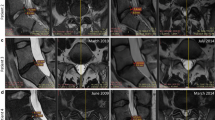

Image analysis

Lumbar spine X-ray imaging showed no decrease in the disc height of the transplanted IVD at the final follow-up at 1 year. The severity of disc degeneration was evaluated using the Pfirrmann grading system (grade I, normal to grade V, most severe degeneration with a collapsed disc) based on conventional T2-weighted sagittal images [29]. We then semiquantitatively analyzed changes in water content using ADC mapping from DWI. In all patients, lumbar endplate Modic changes were absent. All patients had Pfirrmann grades of IV at the time of enrollment. There were no cases where degeneration at the injected IVD was worse at the 12-month follow-up. The six patients who achieved treatment success (pain reduction ≥ 50% and ODI improvement ≥ 50%) showed no increase in Pfirrmann grade at the final follow-up. The Pfirrmann grade of the transplanted L4/5 disc increased from grade IV to grade III at the 6-month and final follow-ups in case 1, who achieved significant VAS improvement at 6 months (Fig. 3). Among the six patients (cases 2, 4, 5, 7, 8, and 9) who achieved treatment success at the final follow-up, cases 4, 8, and 9 showed increased water content based on the ADC map at the 12-month follow-up (Table 4). No osteophyte formation or narrowing of the IVD was observed in any case.

We also evaluated the potential causes of treatment failure (pain reduction < 30% or ODI improvement < 30%) in four patients (cases 1, 3, 6, and 10). In case 1, the patient was overweight and reported significant pain relief for LBP (50% pain relief) at the 12-month follow-up, but the ODI improvement was < 30%. Although the patient was not classified in the treatment success group, notable increases in Pfirrmann grade and in the ADC value were found at the 6-month follow-up (Fig. 3). Initially, case 3 complained of LBP and pain in both buttocks. Initial lumbar X-ray imaging and MRI showed degenerative spondylolisthesis (forward displacement of L4 on L5), facet joint arthritis, and spinal stenosis at the L4/L5 level; flexion and extension radiography showed no lumbar instability (Fig. 4). The patient had no neurogenic intermittent claudication or radiculopathy, which was supported by electromyography and a nerve conduction study. The pain did not improve even after medial branch nerve blocks, and the patient was included in this study based on discographic findings. Case 6 was obese (38 kg/m2) and had a disc protruding to the left side at the L5/S1 level, with a disc height reduction of approximately 21.4%. Case 10 had depressive symptoms (Beck Depression Inventory initial score 14), which might have resulted in treatment failure. Although all patients were enrolled after lumbar medial branch block and discography to rule out other causes of LBP, the LBP was still not successfully eliminated in cases 6 and 10, possibly because of other potential confounding factors for chronic LBP such as obesity (case 6) and depression (case 10). In addition, other structural etiologies for chronic LBP that could have prevented treatment success here may include spondylolithesis (case 3), spinal stenosis (case 3), facet joint arthritis (case 3), decreased disc height (case 6), and disc herniation (case 6) (Fig. 4).

Possible causes of treatment failures in cases 3 and 6. Lumbar lateral X-ray imaging (a), T2 sagittal MRI (b), and T2 axial MRI (c) of case 3 showing degenerative spondylolisthesis of L4 on L5 (slippage or displacement of L4 vertebra compared to L5 vertebra) and spinal stenosis. T2 sagittal MRI (d) and T2 axial MRI (e) of case 9 revealed left-sided L4–5 herniated NP with decreased disc height